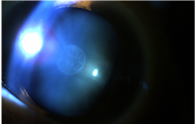

• 백내장 없는 눈

• 백내장 있는 눈

[백내장 질환]

• 20대 후낭하 백내장

• 원모양 핵 백내장

• 피질 백내장

• 심한 백내장으로 인해 실명 된 성숙 백내장